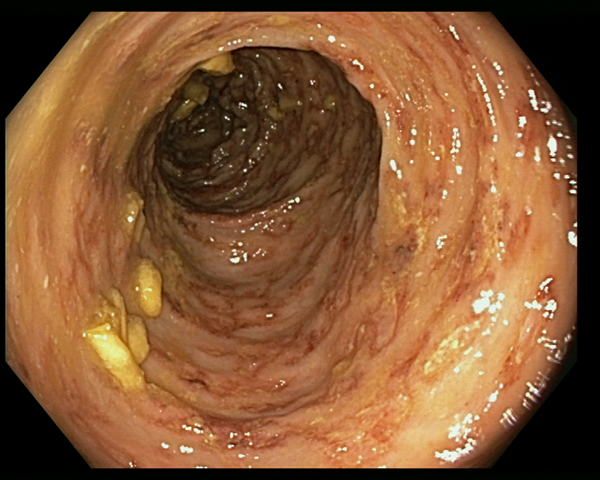

An 84-year-old patient with multiple chronic conditions (arterial hypertension, multifactorial anaemia, chronic obstructive pulmonary disease (COPD), prostatic hypertrophy, gout, diverticulosis of the colon, chronic renal failure) was admitted to the State Hospital in San Marino on the 9 August 2016 for diarrhoea and impaired general condition. Ten months before he had started taking prednisone 25 mg a day for worsening of the COPD, and a few days before admission he had undergone an oesophagogastroduodenoscopy (EGD) for epigastric pain, with evidence of diffuse oedema and hyperaemia of the gastric mucosa, and of an ulcerated polypoid lesion in the second portion of the duodenum. Upon admission, the full blood count showed mild normocytic anaemia (haemoglobin 10.8 g/dl), white blood cells and full blood count were within the normal range of values (in particular eosinophil count was 222 eosinophils/μl), C-reactive protein (CRP) was 5.20 mg/dl (normal values <1). The dose of diuretics already taken by the patient was increased and prednisone was continued; symptomatic treatment and cholestyramine were added. On the 8th day of hospitalisation an antibiotic treatment was started (piperacillin-tazobactam) and steroidal treatment was increased (prednisone was changed to parenteral methylprednisolone 20 mg twice a day) due to worsening respiratory conditions with signs of a pulmonary infiltrate at the chest X rays. However, the respiratory impairment continued worsening, and the patient started having nausea and vomiting with bile and blood. A total body computed-tomography (CT) scan showed diffused tree in bud sings, while excluding involvement of other organs. On the 17th day of hospitalisation, the results of the biopsies performed during EGD were communicated to the clinicians: nematodes compatible with S. stercoralis were present in the duodenal and gastric mucosa (Fig. 2a). In the meantime, S. stercoralis larvae were also found in the microscopic examination of a bronchoalveolar lavage. Microscopic examination of multiple stool and urine samples was negative. Treatment with albendazole 400 mg a day was hence started on the 26 August, and changed 3 days later with ivermectin 200 μg/kg/day following consultation with a tropical diseases specialist. Moreover, steroids were stopped. Nevertheless, the condition progressed to multi-organ failure and the patient died on the 2nd September. Strongyloides serology was positive, but the result was made available only 2 days after the death. Afterwards, previous clinical records were reviewed, showing that the patient had presented eosinophilia: 944 cells/μl in June 2016, 4490 cells/μl in August 2012.

Fig. 2. (a) Histological specimen from gastric biopsies of patient 1. Evidence of numerous S. stercoralis larvae in crypts (H&E 20× magnification). (b) Histological specimen from colonic biopsies of patient 2. Eosinophilic crypt abscess with evidence of Strongyloides larvae and eggs. The surrounding lamina propria shows a dense inflammatory infiltrate rich in eosinophils (H&E 20× magnification).

An 85-year-old patient with moderate-severe chronic renal failure, insulin-dependent diabetes mellitus with peripheral polyneuropathy, COPD, prostatic hypertrophy and rheumatic polymyalgia with probable small-vessel vasculitis was admitted to the State Hospital in San Marino on the 8 March 2017 for fever, asthenia and hyporexia. Blood tests showed hypochromic microcytic anaemia (haemoglobin 9.2 g/dl), mild eosinophilia (558 eosinophils/μl), hyperglycaemia (265 mg/dl), increased erythrocyte sedimentation rate (99 mm/h, normal values <13) and CRP (8.43 mg/dl, normal values <1). Two sets of blood culture were negative. During the first days of hospitalisation, he was kept on his usual therapy, which included prednisone 12.5 mg/day. On the 13th March a contrast-enhanced CT scan was done, showing diffuse bowel and gastric wall thickening, thickening of the bronchial walls and pulmonary interstitial oedema. A colonoscopy demonstrated a flat lesion in the right colon, intestinal inflammation, ulcers and petechial spots (Fig. 3). The histological examination revealed lymphoplasmacellular and eosinophilic infiltration, epithelioid granuloma and multiple S. stercoralis larvae (Fig. 2b). Also, intranuclear inclusion bodies compatible with cytomegalovirus (CMV) infection were found; this infection was confirmed by PCR on blood, that showed 1888 UI/l viraemia. On the 16 March treatment with ivermectin 200 μg/kg/day and piperacillin/tazobactam 2.25 g three times a day (dosage adjustment for renal failure) was started. The dose of prednisone was gradually reduced. In the meantime, also stool examination, PCR and IFAT resulted in positive for S. stercoralis. Hence, on the 20 March, albendazole 400 mg twice a day was added. The general condition of the patient gradually improved, and CMV viraemia reduced spontaneously along with clinical recovery. Antihelminthic therapy was stopped 2 weeks after negativisation of stool microscopy, that was achieved after 21 days of treatment. The patient was discharged on the 7th April, in fair clinical condition. On the 30 May, he underwent a colonoscopy that showed almost complete resolution of the inflammation. The biopsy of the flat lesion (observed also in the previous examination) demonstrated a villous adenoma.